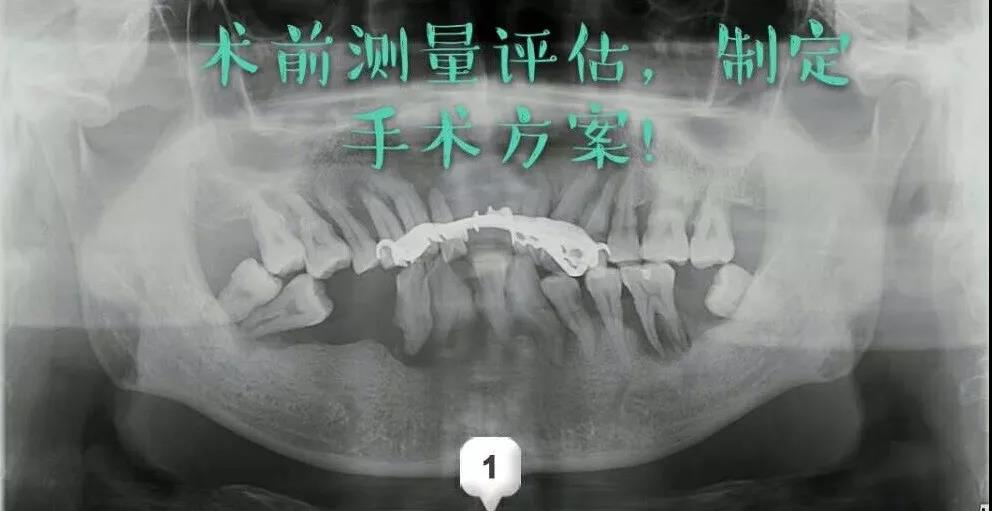

第一次耗时两个多小时:先进行了术前的测量评估,指定手术方案;术中采用数字化种牙导板,精准定位;逐级备洞,植入植体,扭力复合完成植入上半口。